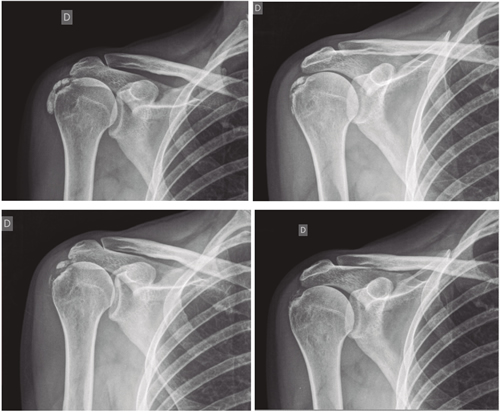

Figura 1

Resultados: Edad media: 54,6 años (n = 138); mujer (73,1 %; n = 101); proporción mujer/hombre 3: 1; tendón supraespinoso (94,6 %; n = 124); subescapular (5,4 %; n = 14); hombro izquierdo (55,1 %; n = 76), hombro derecho (44,9 %; n = 62); bilateral 1,4 % (n = 2); diestros 96,3 % (n = 133); antecedentes personales: tabaquismo (19,5 %; n = 27), diabetes (7,2 %; n = 10). El tiempo de enfermedad promedio fue de 6,08 meses. Dolor agudo-subagudo (menos de 3 meses) 47,1 %; (n = 65), dolor crónico (más de 3 meses) 52,9 % (n = 73). Tipo radiológico: formativo 75,3 % (n = 104), resortivo 24,7 % (n = 34). Número promedio de sesiones: 20. Complicaciones del tratamiento 2,8 % (n = 4): intolerancia/eritema/quemadura. Ocupación: administrativo 39,8 % (n = 55), trabajos manuales 60,2 % (n = 83). El dolor inicial EVA de 7,3 puntos disminuyó significativamente (p = 0,0000) después del tratamiento a 2,7. El tamaño promedio inicial de las calcificaciones fue de 10,7 mm y disminuyó significativamente (p = 0,0000) después del tratamiento a 3,8 mm. Cambio de calcificación: tasa de éxito/curación 55,7 % (n = 77), tasa de mejora 20,2 % (n = 28); tasa de fracaso del 23,9 % (n = 33). La limitación funcional disminuyó de un 10,8 % a un 2,1 %.

Results: Mean age 54.6 years (n = 138). Female (73.1 %; n = 101); female to male ratio 3:1. Supraspinatus tendon (94.6 %; n = 124), subscapularis (5.4 %; n=14); left shoulder (55.1 %; n = 76), right shoulder (44.9 %; n = 62). Bilateral 1.4 % (n = 2). Right handed 96.3 % (n = 133); Personal history: smoking (19.5 %; n = 27), diabetes (7.2 %; n = 10); disease time averaged 6.08 months; acute-subacute pain (less than 3 months) 47.1; (n = 65), chronic pain (greater than 3 months) 52.9 % (n = 73). Radiological type: formative 75.3 % (n = 104); resorptive 24.7 % (n = 34). Average number of sessions: 20.5. Treatment complications 2.8 % (n = 4): intolerance/erythema/burn. Occupation: administrative 39.8 % (n = 55), manual jobs 60.2 % (n = 83).

Average initial pain 7.3 points (VAS scale), significantly decreased (p = 0.0000) post treatment to 2.7. Initial average size of calcifications 10.7 mm and significantly decreased (p = 0.0000) post treatment to 3.8 mm. Change of calcification: success/cure rate 55.7 % (n = 77), improvement rate 20.2 % (n = 28); failure rate 23.9 % (n = 33). Functional limitation decreased from 10.8 % of patients to 2.1 %.